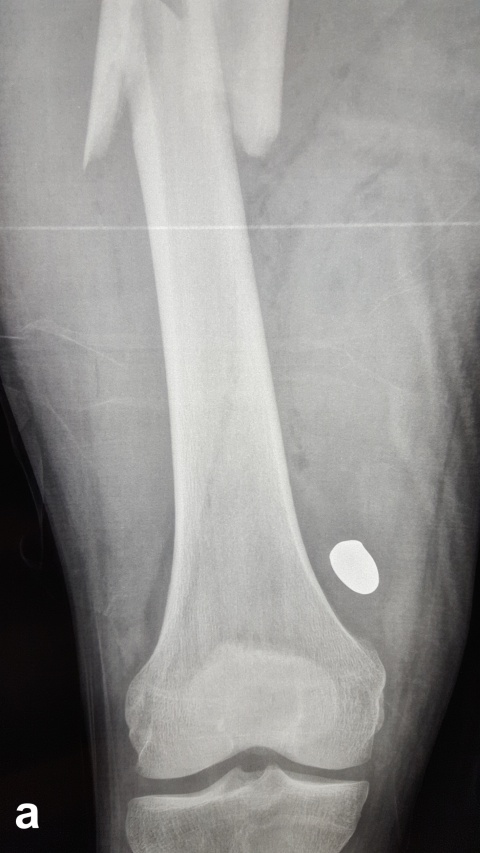

Beim Auftreffen des Projektils im Rahmen von Niedrigenergieverletzungen auf Knochengewebe entsteht meist eine typische, einfache Fraktur (Abbildung 2). Hochenergieverletzungen des Knochens münden in eine multifragmentäre Situation, bei der ein Großteil der Projektilenergie an den Knochen abgegeben wird. Insbesondere lange Röhrenknochen können, da sie wie eine starre, spröde flüssigkeitsgefüllte Röhre agieren, durch Projektile mit hoher Energie explosionsartig zerstört werden (Abbildung. 3).

Insbesondere bei Schussfrakturen verursacht durch Hochenergieprojektile ist neben ausgeprägten Weichteilverletzungen mit einer massiven Trümmerzone aus avitalen Knochenfragmenten zu rechnen. In diesen Fällen muss ein radikales Débridement sowohl der avitalen Weichteile, aber auch der avitalen Knochenfragmente erfolgen [1]. Aufgrund der hohen Kontaminationsrate durch in den Schusskanal gezogene Kleidungsreste und Fremdkörper mit entsprechend erhöhtem Infektionsrisiko [21, 43], ist die primäre Stabilisierung durch einen Fixateur externe das Mittel der Wahl [1]. Dies gilt insbesondere dann, wenn nicht eindeutig ist, ob um eine Niedrig- oder Hochenergieverletzung vorliegt. Dieses Vorgehen wird durch die Publikation von Long et al. [44] unterstützt. In dieser Arbeit bezüglich der Schussverletzungen am Femur wurde anhand von klinischen und radiologischen Befunden eine Einteilung in 3 Schweregrade vorgenommen. Während Grad-1-Verletzungen Niedrigenergieverletzungen waren, die allesamt primär mit einem Marknagel versorgt wurden, wiesen Grad-2- und Grad-3-Verletzungen Zeichen einer Hochenergieverletzung auf. Diese Patienten entwickelten im Verlauf in bis zu 50 % der Fälle eine tiefe Wundinfektion, was eindeutig gegen eine primäre osteosynthetische Ausversorgung spricht. Zudem waren bei Verletzungen der Grade 2 und 3 auch wiederholte Débridements notwendig.

der Schussfraktur des rechten Femurs zudem das noch oberhalb des Kniegelenks befindliche Projektil.

c: Klinisch bestehen ein Ein- und Ausschuss am linken Oberschenkel (rechter Bildrand) mit isolierter und unkomplizierter Weichteilverletzung sowie ein isolierter Einschuss am rechten Oberschenkel medial ohne dazugehörigen Ausschuss. Es wurde nur ein Schuss abgegeben.